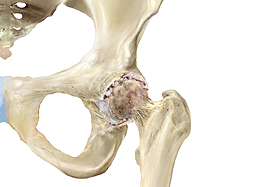

Die häufigsten Ursachen für Hüftschmerzen und Knieschmerzen sind abnutzungsbedingte Veränderungen des Gelenkes sowie auch unfallbedingte Verletzungen  (Knie- und Hüftverletzungen) und Verletzungsfolgen wie beispielsweise Hüftarthrose, Kniearthrose, gelenknahe Knochenbrüche, Meniskusrisse, Kreuzbandrisse.

Behandlungen von Hüft- und Kniegelenksverletzungen und degenerative abnutzungsbedingte Leiden sind eine unserer Spezialitäten, so zum Beispiel Kunstgelenkersatzoperationen an Hüfte und Knie, als auch Knochenbruchbehandlungen insbesondere hüftgelenksnahe Frakturen, Oberschenkelbrüche oder auch Knochenbrüche unter Mitbeteiligung des Kniegelenkes. Eine unserer weiteren Spezialitäten ist die Behandlung von Meniskus- und Kreuzbandrissen. Die Entwicklungen auf diesem Fachgebiet sind enorm vorangeschritten, sodass heute viele Eingriffe in entsprechender arthroskopischer oder minimal-invasiver Technik durchgeführt werden können. Dies führt in der Regel zu bedeutend kürzeren Spitalaufenthalten. Für weitere Informationen wenden Sie sich an unsere Praxis, kontaktieren uns via Kontaktformular oder entnehmen Informationen aus den nebenstehenden Links. Doch was ist eigentlich Arthrose? Lesen Sie auf diesem Link weiter!